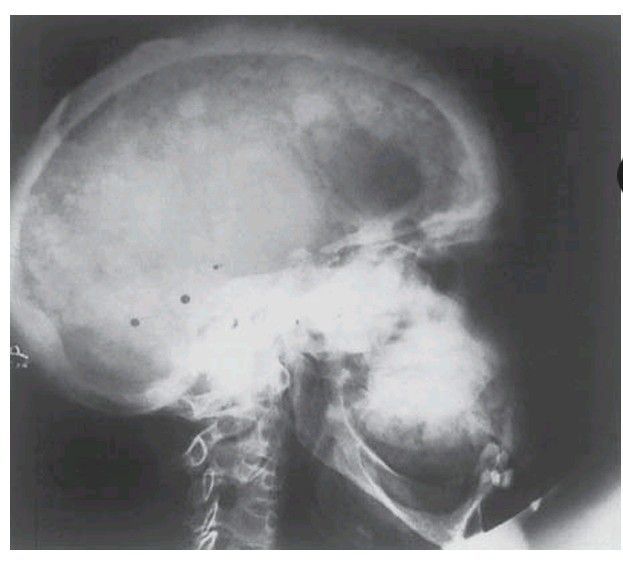

Paget’s disease of the skull and maxilla. The thickening of the bone and the irregular areas of sclerosis and resorption, which give it a f l uffy appearance, are in striking contrast to the unaffected mandible.